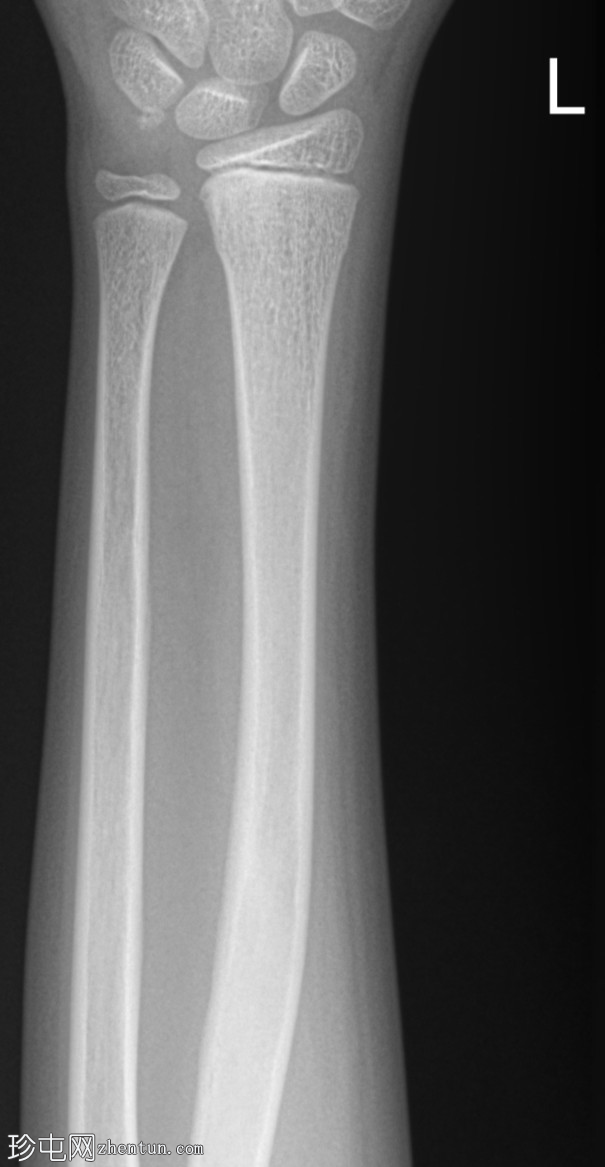

正位片

桡骨远端干骺端皮质骨隆起,符合骨性骨折(Cuckle fracture)的特征。

骨性骨折(Cuckle fracture)是指长骨干的不完全性骨折,其特征是皮质骨隆起;常见于儿童,常累及桡骨远端干骺端。